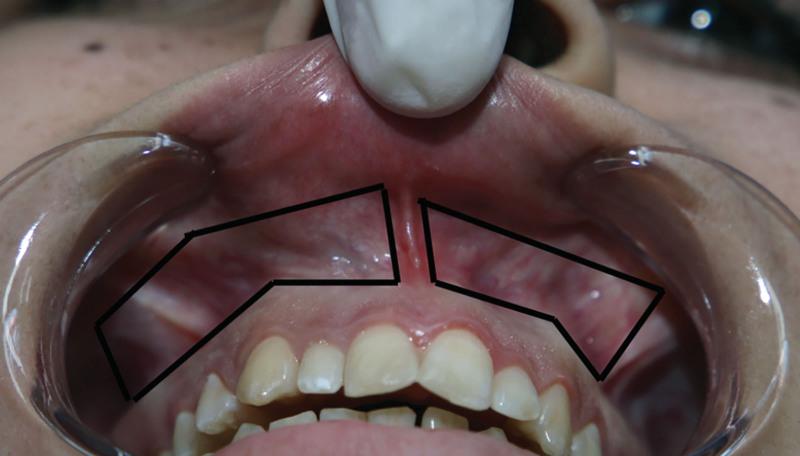

The present study was performed to evaluate the differences in the efficacy of treating excessive gingival display with the standard modified lip repositioning surgery or the modified lip repositioning surgery with dual-layered suturing.

This study included 20 female patients who had a gummy smile resulting from upper lip hypermobility or short upper lip. Preoperative measurements of the amount of gum exposure were taken during involuntary smiling. The patients were randomly divided into two groups; the first group was treated with the standard technique, whereas the second group was treated with the double-layered suturing method. All patients were followed up at 14 days, 3 months, and 6 months; postoperative assessment was done by measuring the changes in the gingival display during spontaneous smiling.

Postoperative measurements at 14 days follow-up showed a significant reduction in the amount of gingival exposure in both groups. However, at 3 months, there was a complete relapse for the first group of patients, whereas the second group showed a slight regain in the amount of gum exposure, though the latter group showed a complete relapse at 6 months postoperative.

The dual-layered suturing for the modified lip repositioning surgery did not provide any long-term improvement for treating gummy smile patients; however, it did delay the relapse to a certain extent for the first 3 months postoperative in some of the patients.